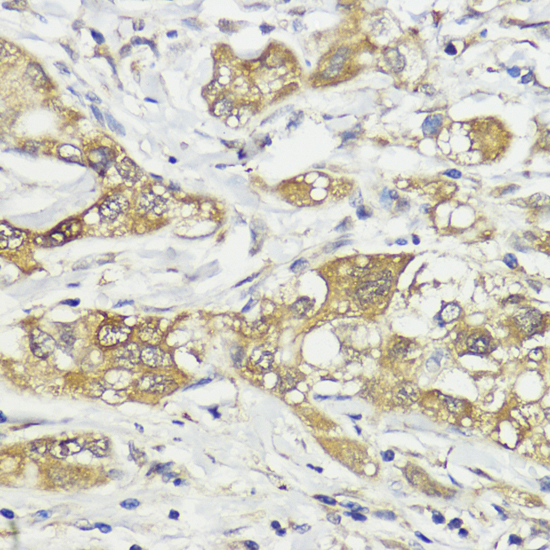

Immunohistochemistry of paraffin-embedded human colon using HACE1 at dilution of 1:100 (40x lens).

Immunohistochemistry of paraffin-embedded human liver cancer using HACE1 at dilution of 1:100 (40x lens).